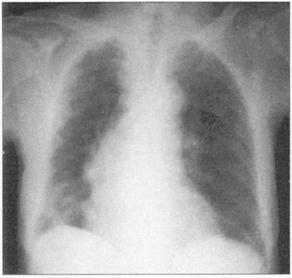

①周围性发绀及周围静脉扩张是由COPD引起的CO2潴留的主要特征(图76)。②脊柱侧后凸常预示患者有某种呼吸系统疾病的倾向(图77)。③结核的X线表现(图78)。④肺尖部结核所致的纤维化多引起上胸部变平(图79),由于脊柱常受累,故多有成角。⑤支气管肺癌(图80)。⑥大叶肺炎患者常伴发单纯疱疹病毒感染(图81、图82)。⑦如肺组织萎陷(如气胸),则胸片上无法看到肺纹理(图83)。

图81 大叶性肺炎,这个患者有右肺实变

图82 单纯疱疹病毒感染在大叶性肺炎患者常见